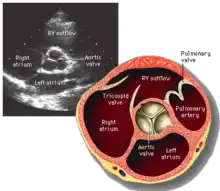

La válvula aórtica normalmente tiene tres valvas o cúspides de forma semilunar.[Nota 1] Suelen llamarse cúspide coronaria izquierda, cúspide coronaria derecha y cúspide no coronaria.[Nota 2] Cada valva está separada de la vecina por una comisura.[2][3][4][5]

Desde el punto de vista anatómico, cada valva puede dividirse en varias regiones, el borde libre en cuyo centro existe una zona engrosada que se denomina nódulo de Arancio, el cuerpo de la valva y la región de inserción. En el espacio comprendido entre cada una de las tres valvas y la pared arterial se forma una pequeña cavidad con forma de saco que se llama seno aórtico o seno de Valsalva, en dos de estos senos se encuentra el origen de las arterias coronarias.[6] La unión sinotubular es el punto en la aorta ascendente donde terminan los senos aórticos y la aorta se convierte en una estructura tubular.

La válvula aórtica está situada detrás de la válvula pulmonar, en la enfermedad congénita llamada transposición de los grandes vasos, la situación de estas dos válvulas se invierten, la válvula anterior es la válvula aórtica.